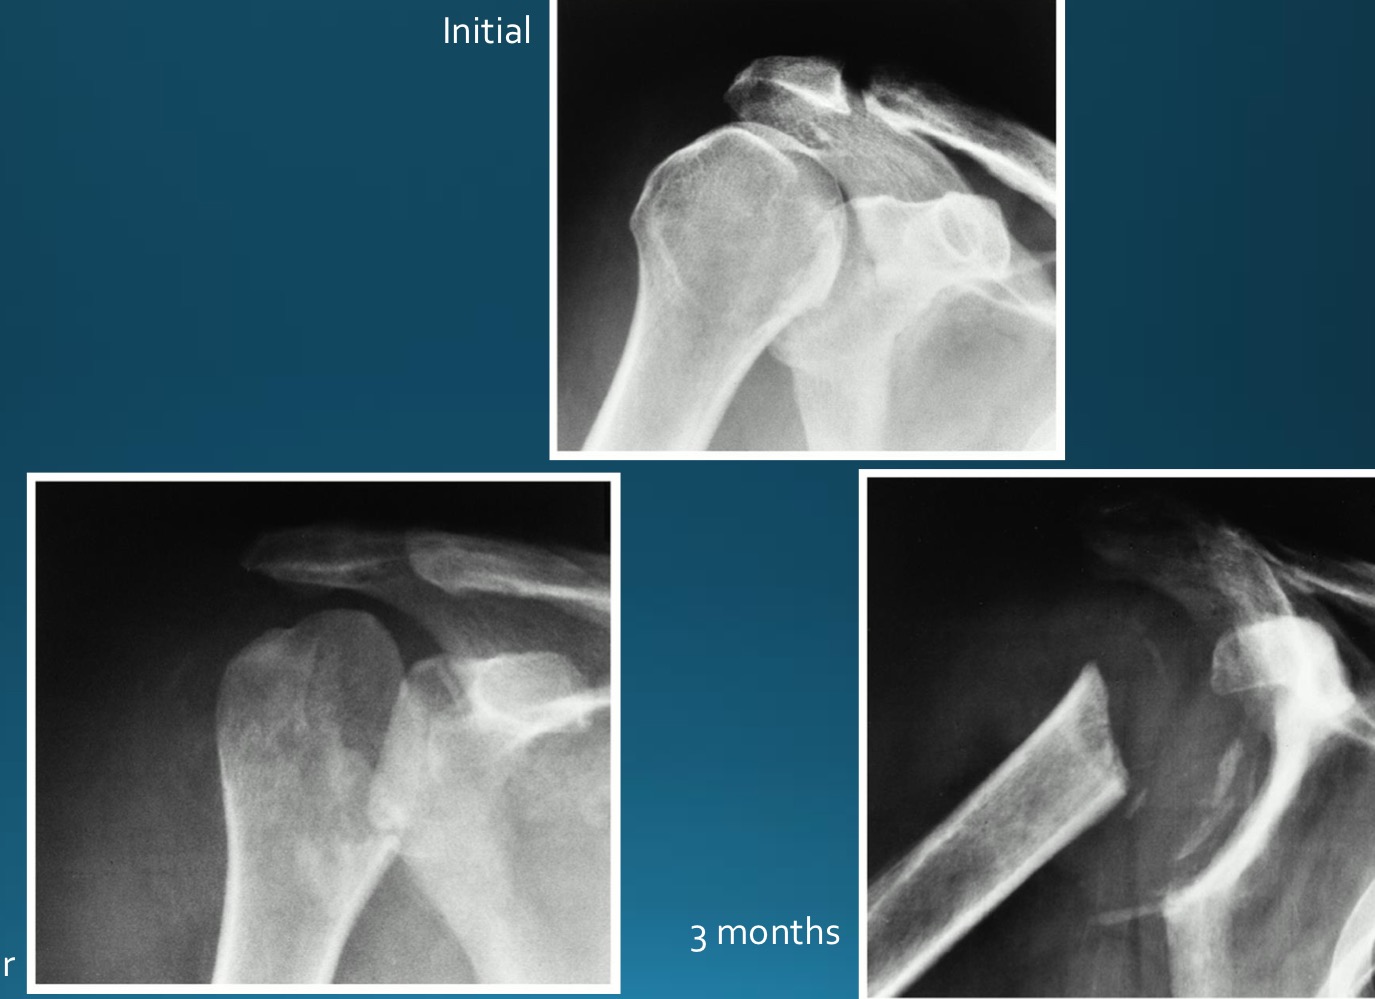

what would this charcot joint be caused by

syphilis

syringomyelia